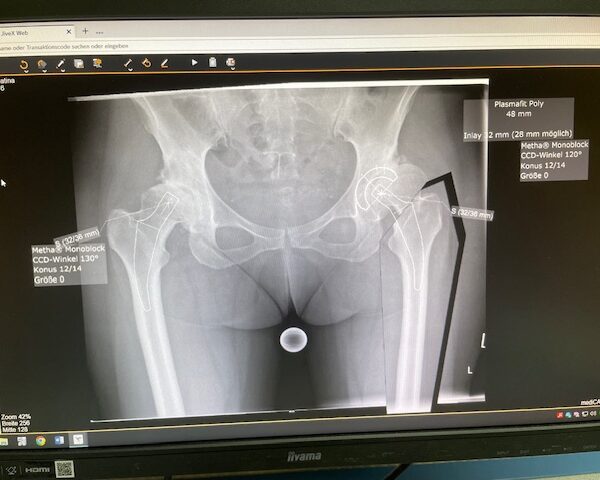

Ο προεγχειρητικός ψηφιακός σχεδιασμός

Ο προεγχειρητικός ψηφιακός σχεδιασμός ήταν ιδιαίτερα μεθοδικός και συγκεκριμένος. Η ακτινογραφία λεκάνης της ασθενούς εισήχθη σε ειδικό λογισμικό στον υπολογιστή, το οποίο επέτρεψε τον ακριβή προγραμματισμό της καινούριας θέσης της άρθρωσης.

Μέσω του ψηφιακού αυτού σχεδιασμού, υπολογίστηκε με ακρίβεια το μέγεθος και ο τύπος των προθέσεων, η γωνία του κώνου, καθώς και η σωστή ανατομική τοποθέτηση των μοσχευμάτων. ώστε να επιτευχθεί τέλειος ισοσκελισμός των κάτω άκρων και να αποφευχθεί οποιαδήποτε διαφορά μήκους μετεγχειρητικά!!!

Πρόκειται για ένα εξαιρετικά σημαντικό στάδιο, καθώς εξασφαλίζει τη μέγιστη δυνατή ακρίβεια, ταχύτητα και αποτελεσματικότητα κατά τη διάρκεια της επέμβασης. Επιπλέον, συμβάλλει στην άριστη λειτουργικότητα του ισχίου καθώς και να επιτευχθεί τέλειος ισοσκελισμός των κάτω άκρων και να αποφευχθεί οποιαδήποτε διαφορά μήκους μετεγχειρητικά!!!

Ο προεγχειρητικός ψηφιακός σχεδιασμός αποτελεί πάντα πλήρως εξατομικευμένο πλάνο, προσαρμοσμένο στα ανατομικά χαρακτηριστικά και τις ανάγκες του κάθε ασθενούς, και είναι καθοριστικός για την επιτυχία της επέμβασης !!!